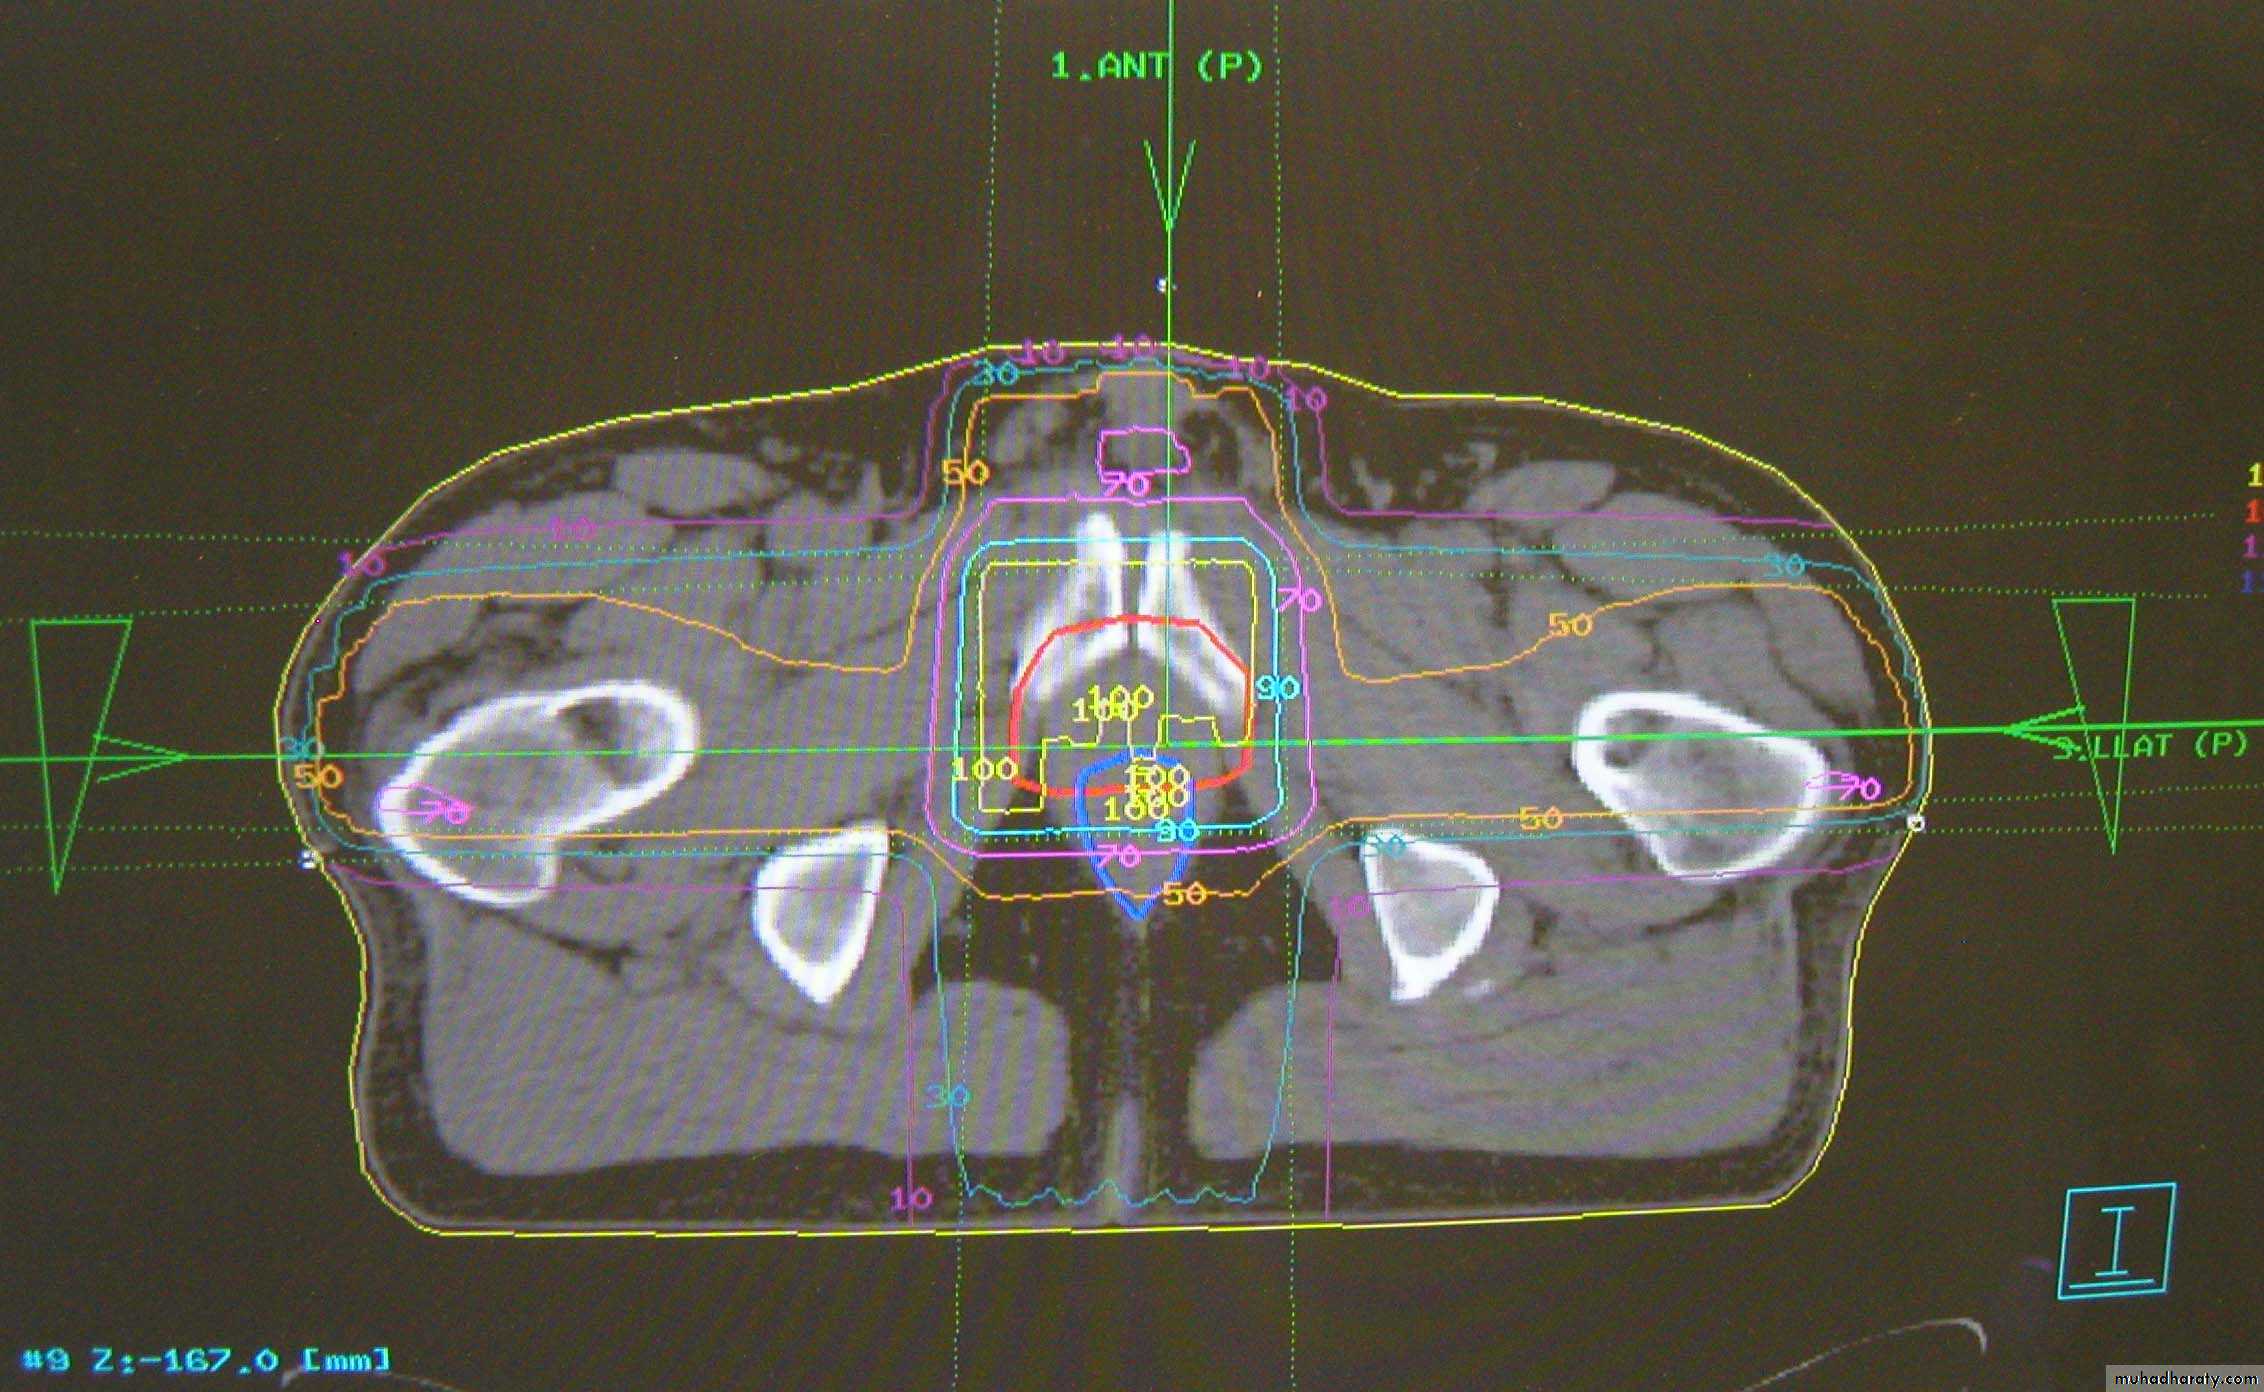

Radical treatments – complex multi-field treatment plans using image sets and customised field shapes

(prostate, bladder, head & neck sites, radical brain tumours, early breast)

Need to deliver a high, even dose to the tumour, whilst avoiding normal and sensitive tissue

Localisation of tumour volume is very important

3D Conformal prostate plan with MLC